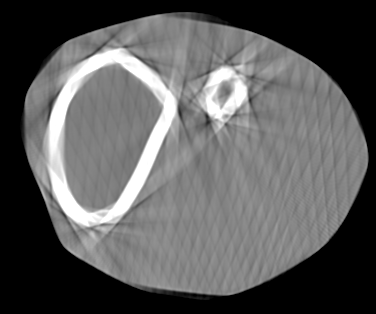

Involuntary subject motion is the main source of artifacts in weight-bearing cone-beam CT of the knee. To achieve image quality for clinical diagnosis, the motion needs to be compensated. We propose to use inertial measurement units (IMUs) attached to the leg for motion estimation. We perform a simulation study using real motion recorded with an optical tracking system. Three IMU-based correction approaches are evaluated, namely rigid motion correction, non-rigid 2D projection deformation and non-rigid 3D dynamic reconstruction. We present an initialization process based on the system geometry. With an IMU noise simulation, we investigate the applicability of the proposed methods in real applications. All proposed IMU-based approaches correct motion at least as good as a state-of-the-art marker-based approach. The structural similarity index and the root mean squared error between motion-free and motion corrected volumes are improved by 24-35% and 78-85%, respectively, compared with the uncorrected case. The noise analysis shows that the noise levels of commercially available IMUs need to be improved by a factor of $10^5$ which is currently only achieved by specialized hardware not robust enough for the application. The presented study confirms the feasibility of this novel approach and defines improvements necessary for a real application.